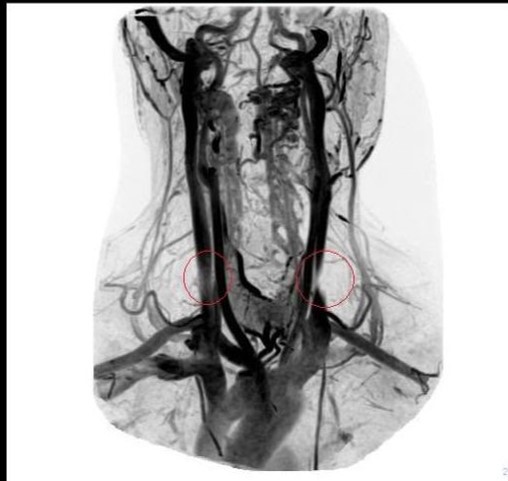

A Vascular connection to Multiple Sclerosis

ccsvi-veins-edit